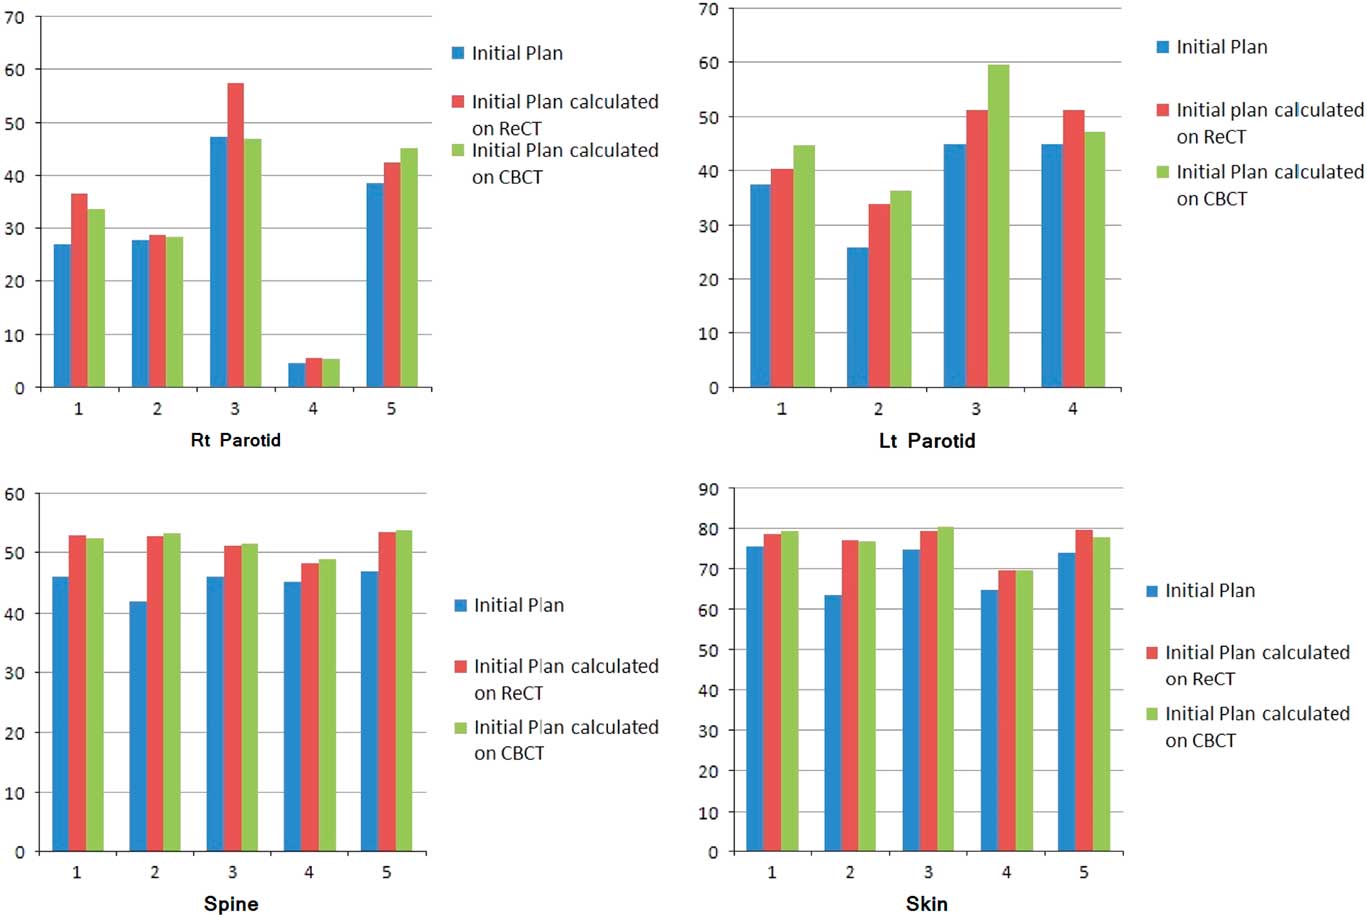

Re-scanning and re-planning at 20th fraction of the treatment shows 27% (13–42%) reduction in parotid volumes (Figure 2), and therefore 21% (7–35%) increase in parotid mean doses. Initial plan calculated on ReCT and CBCT found 15% (9–26%) increase in planning risk volume (PRV) spine maximum doses, which were reduced by re-planning on ReCT. The body maximum doses increased by 6·5% (4–8%) in four patients and 22% in one patient when initial CT plan was calculated on ReCT and CBCT. These results showed a statistically significant difference in the parotids, PRV spine and skin doses with a p-value of 0·01, 0·007 and 0·02, respectively. Figure 3 is the graphical representation of mean doses of parotids and maximum doses of PRV spine and skin in all three plans (initial CT plan, initial plan calculated on ReCT and CBCT).

Figure 3 Graphical representation of mean doses of parotids and maximum doses of PRV spine and skin in all three plans of five patients.